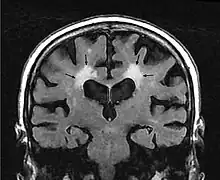

En la Tomografía Computarizada, la leucoaraiosis se observa como regiones con menor densidad, mas oscuras que las circundantes, es decir áreas hipodensas, en Imagen por Resonancia Magnética se define como lesiones con mayor intensidad de señal es decir áreas hiperintensas, por presentar un aspecto más brillante que las zonas aledañas. Estas imágenes pueden verse en las regiones próximas a los ventrículos cerebrales, corona radiata y centro semioval.[9] Se han utilizado escalas cualitativas como la de Fazekas para determinar el grado de las lesiones:

- Grado 0 corresponde a ausencia de lesión.

- Grado 1 lesiones focales.

- Grado 2 lesiones confluentes iniciales.

- Grado 3 cuando las lesiones difusas son muy extensas y comprenden regiones cerebrales completas.